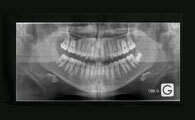

L’orthodontie consiste à déplacer les dents et à modifier la croissance des mâchoires, afin d'obtenir un alignement dentaire harmonieux et d'améliorer les fonctions orales. Un orthodontiste est un chirurgien-dentiste, spécialisé en orthopédie dento-faciale.